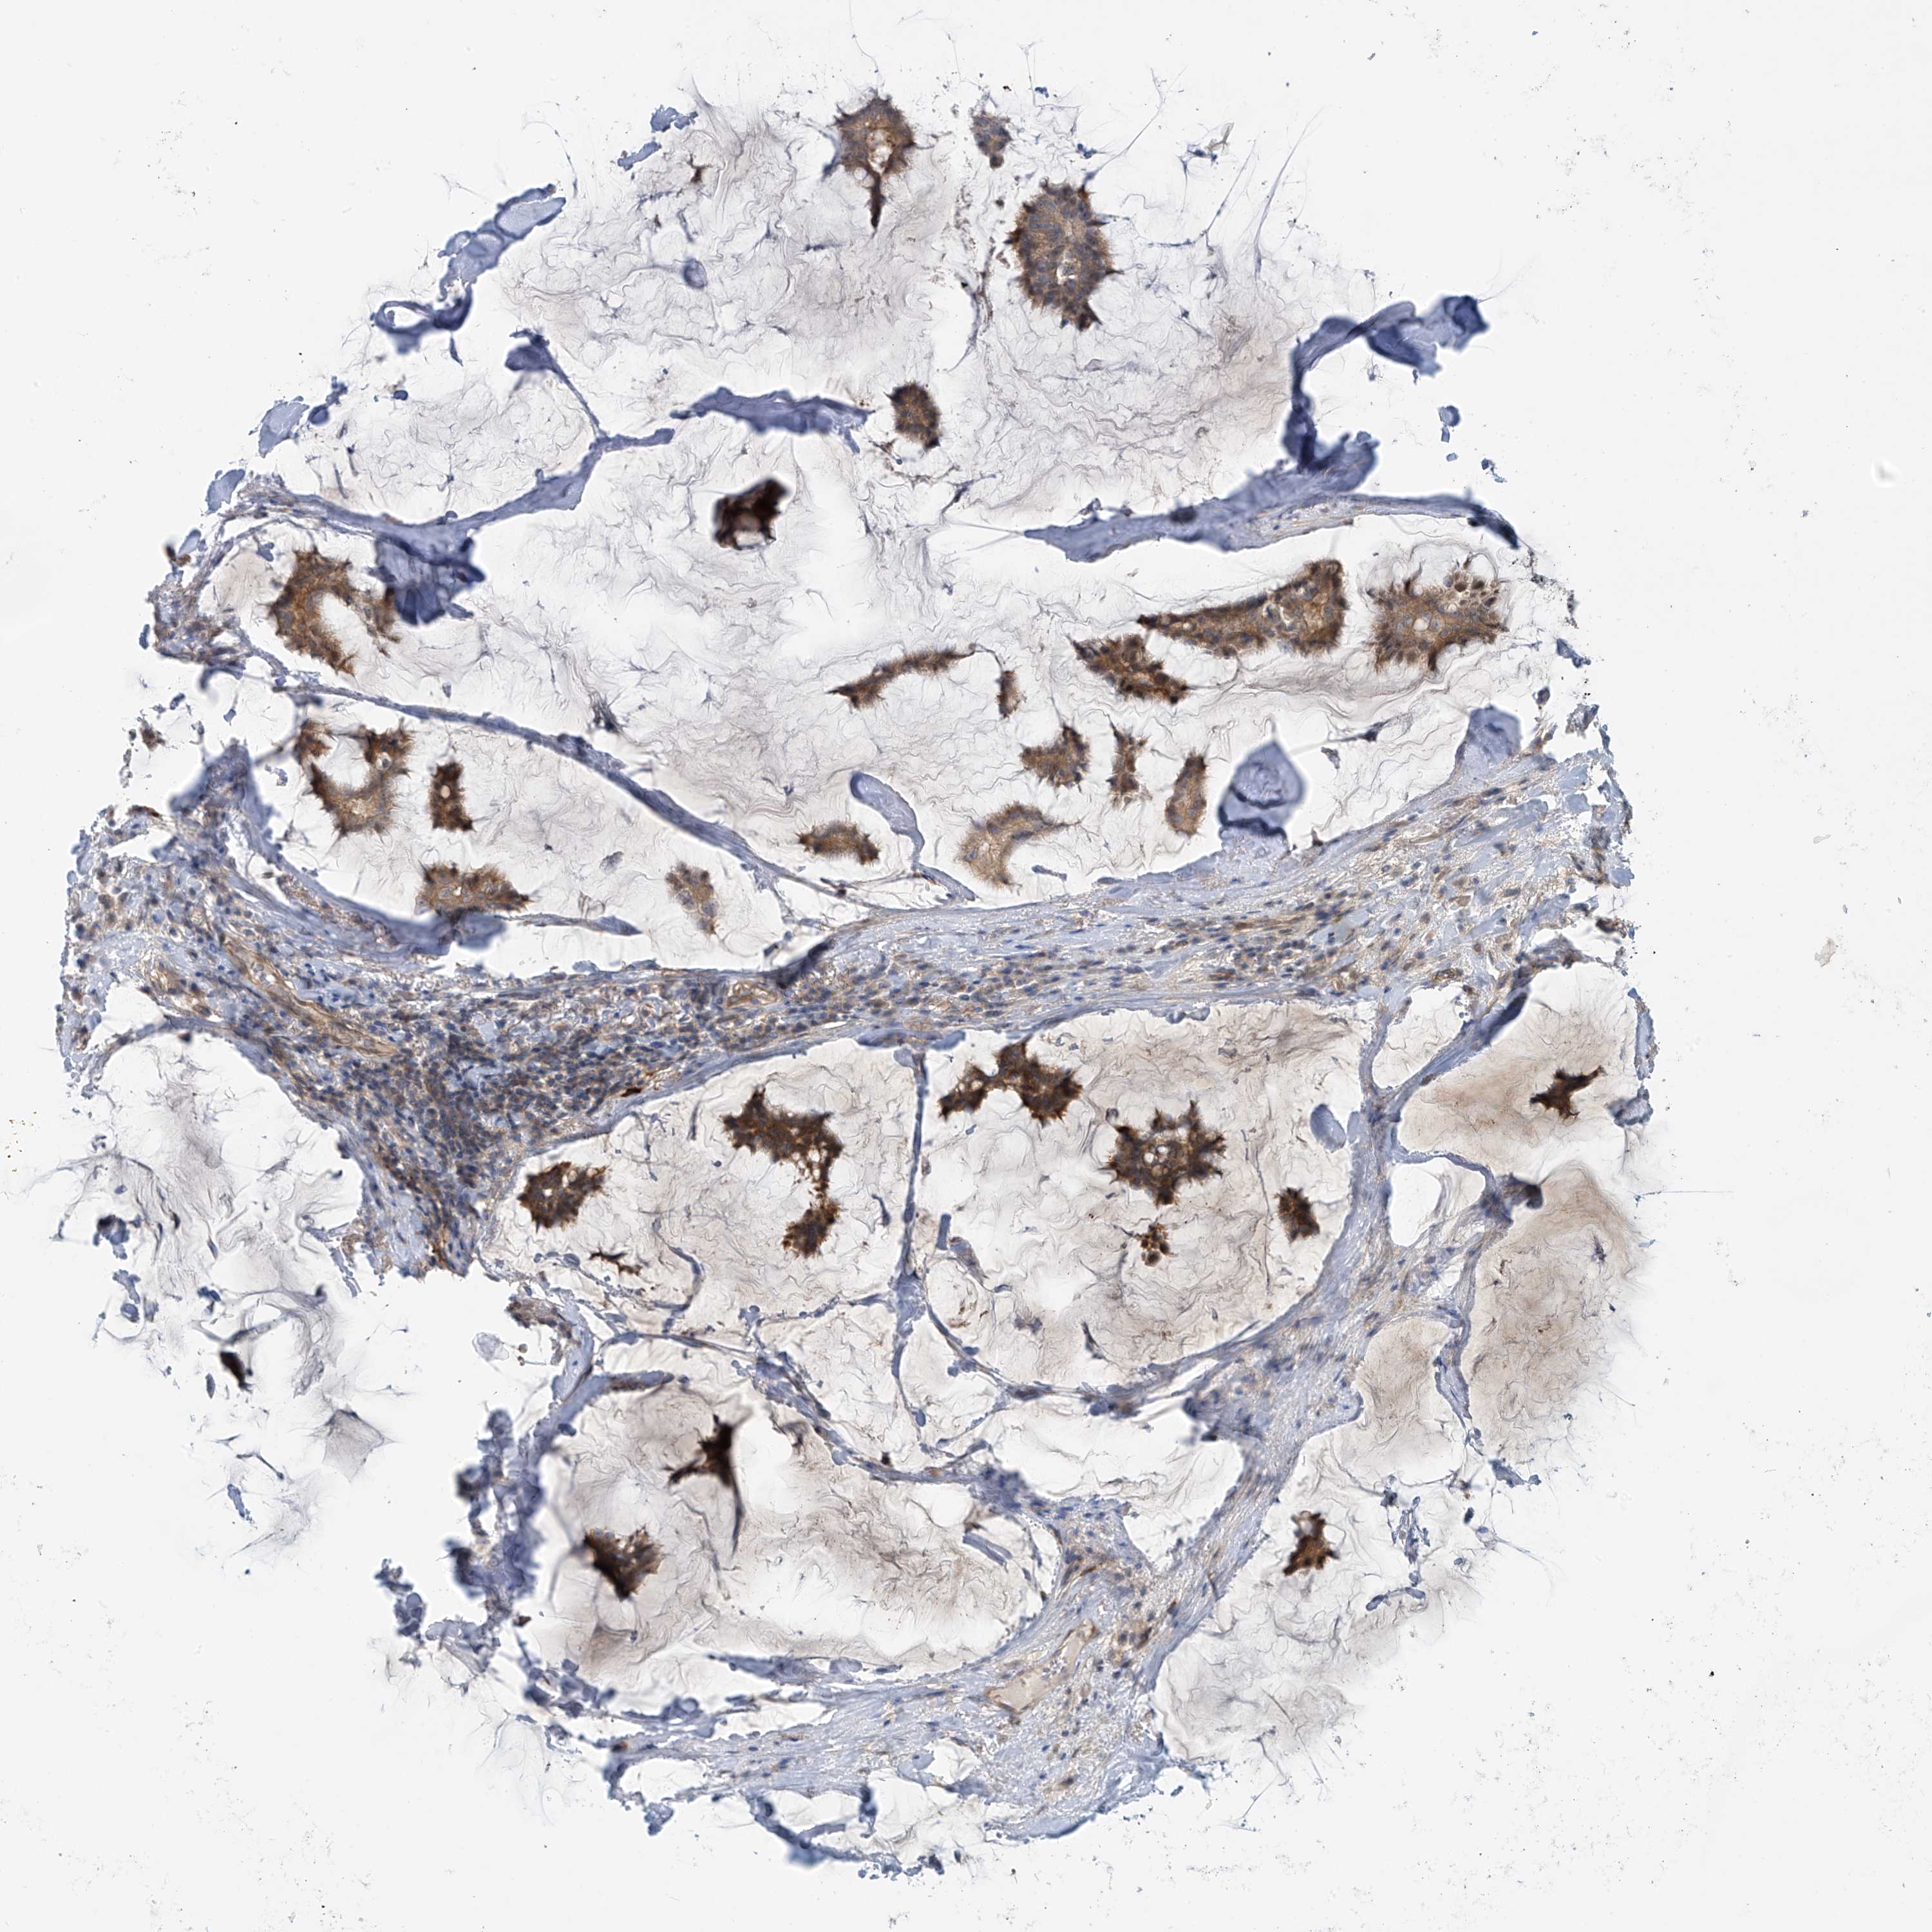

CANCER BREAST CANCER Show tissue menu

BRCA TCGA BRCA VALIDATION PROTEIN EXPRESSION